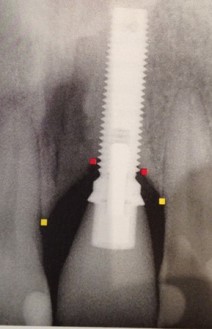

É a substituição do dente ou dentes perdidos, com a colocação de pinos de titânio e posterior colocação de prótese.

Clique na imagem para ampliar: